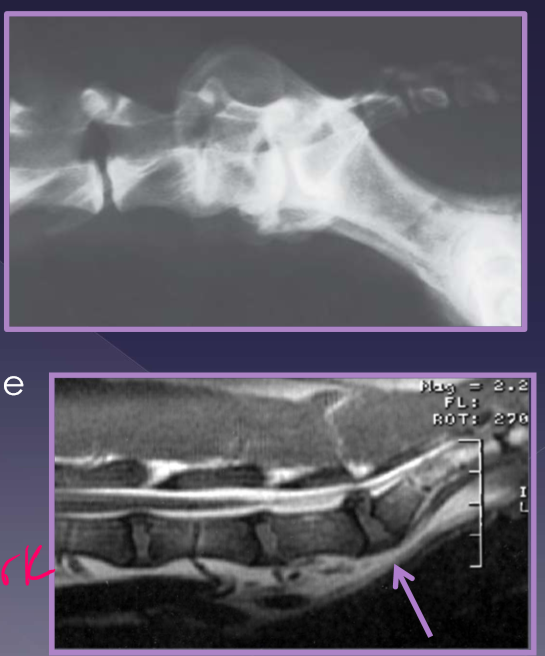

Atlantoaxial instability

compression and concussion of cranial cervical spinal cords

displacement of vertebrae into spinal canal

C2 dorsally displaced from C1

due to:

ligamentous instability

osseous abnormality

congenital or traumatic

effect:

excessive flexion of the A-A joint

cranial axis displaces dorsally in relation to atlas

abnormalities

aplasia of the dens - 46%

hypoplasia of the dens - 34%

dorsal dens angulation

separation of the dens

up to 24% of dogs with A-A instability have an normal dens

diagnosis for atlantoaxial instability

physical examination: Do not flex the neck! makes C2 go dorsally and makes pain worse in flexion of neck

radiographs

increased distance between dorsal arch of C1 and dorsal spinous process of C2

CT

MRI